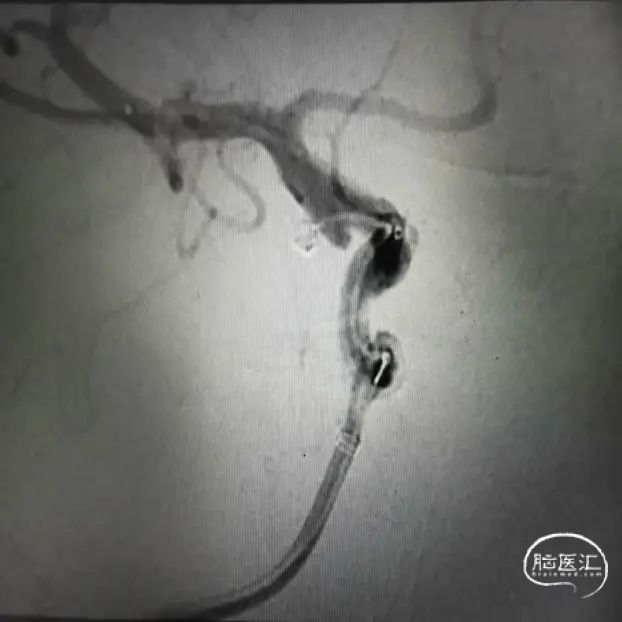

栓塞第一枚弹簧圈

栓塞第二枚弹簧圈

穿刺右股动脉,造影证实右侧后交通动脉瘤,微小宽颈动脉瘤,5F多功能造影管带通桥银蛇6F-115直奔主题,进入右侧颈内动脉,路径图指引下微导管引导支架微导管到达预定位置,然后通过微导丝引导栓塞导管进入瘤腔,分别依次填入3D2*4cm、1.5*2cm、1*1cm三枚弹簧圈,栓塞结束后造影显示动脉瘤致密栓塞,依次撤出器械,结束手术。